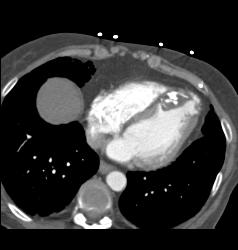

Prior Myocardial Infarction